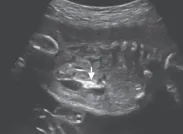

7.单脐动脉

单脐动脉指胎儿脐带内仅有1根脐动脉和1根脐静脉(正常由2根脐动脉和1根脐静脉组成)。

单脐动脉胎儿约30%合并其他结构畸形,如心血管、泌尿生殖系统、骨骼系统、神经系统和胃肠道等畸形。

需进行详细的结构检查,预后取决于合并畸形的严重程度。如果单脐动脉合并其他畸形或胎儿生长受限,应进行介入性产前诊断。